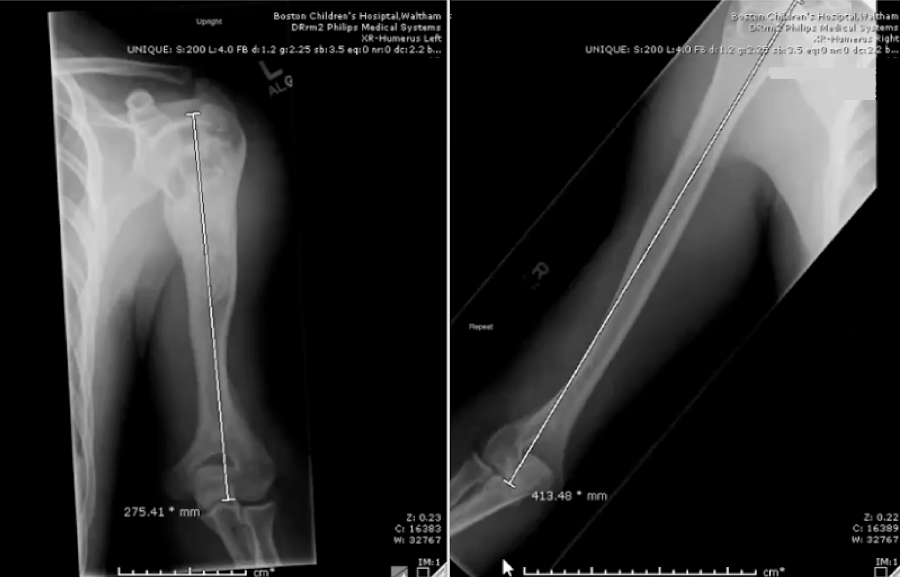

Complex case: Humeral lengthening using a lower extremity device

Treatment to remove a bone cyst in this patient’s upper left arm when he was 8 years old stopped further growth in that arm. By the time he was 18, his right arm had grown 138 millimeters longer than his left. Over the course of two summers, surgeons in the Limb Lengthening and Reconstruction Program lengthened his left arm using the PRECICE Nail internal lengthening device.